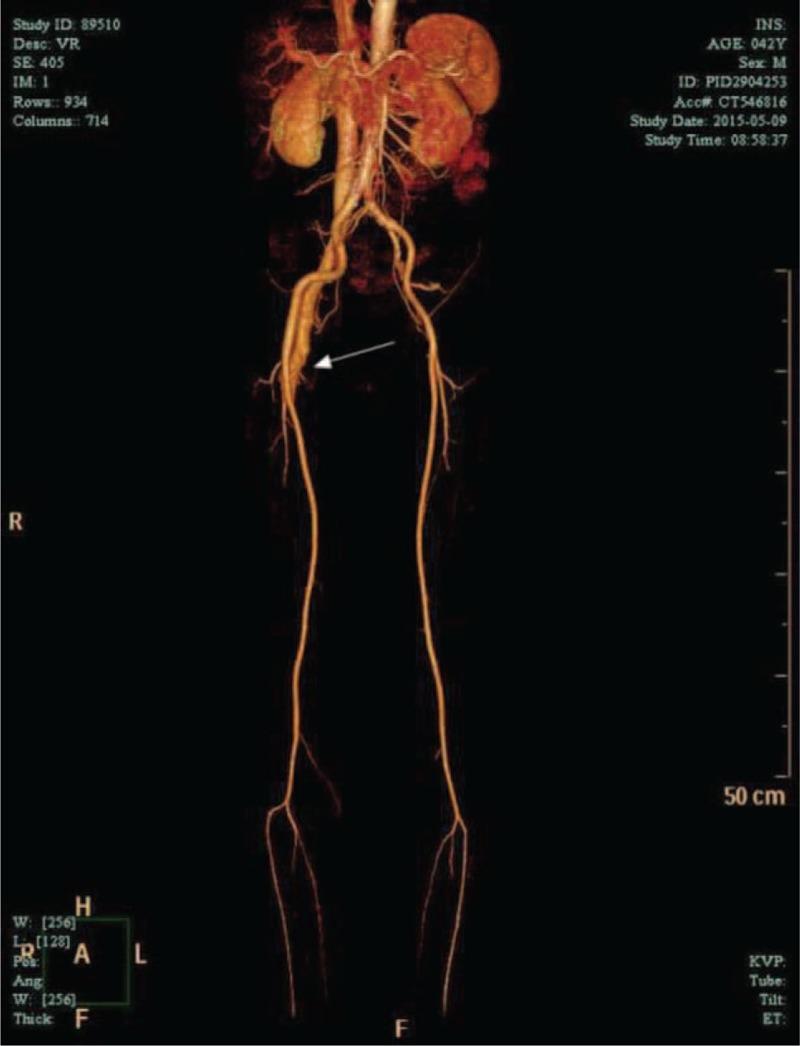

Double-lumen catheters have been used widely to obtain temporary access in patients who are in need of acute hemodialysis (HD) because of acute renal failure. Several complications are associated with the insertion of these catheters, including bleeding, infection, injuries to arteries, and deep venous thrombosis. An arteriovenous fistula (AVF) is a rare but significant complication following catheterization for temporary HD. Herein, we present a case of AVF associated with leg swelling 6 months after the removal ofa double-lumen HD catheter. We describe a special case of a 42-year-old man who experienced acute renal failure secondary to diabetic ketoacidosis (DKA). A 12-Fr dialysis catheter was inserted in the right femoral vein. Six months after catheter removal, the patient was admitted for pain and swelling in the right leg. Color Doppler ultrasound and three-dimensional computed tomography (CT) revealed an AVF between the right femoral vein and the right femoral superficial artery. The fistula was repaired successfully by vascular surgeons. This case highlights that an AVF is a rare but significant complication after catheterization for temporary HD. The nephrologist should be wary of the potential of this complication and perform clinical and medical examinations at the insertion and removal of temporary HD catheters.

双腔导管已被广泛用于因急性肾衰竭而需要进行急性血液透析(HD)的患者,以获得临时通路。这些导管的插入会引发多种并发症,包括出血、感染、动脉损伤和深静脉血栓形成。动静脉瘘(AVF)是临时HD导管插入术后一种罕见但严重的并发症。在此,我们报告一例在拔除双腔HD导管6个月后出现与腿部肿胀相关的AVF病例。我们描述了一名42岁男性的特殊病例,该患者继发于糖尿病酮症酸中毒(DKA)而出现急性肾衰竭。在右股静脉插入了一根12F透析导管。导管拔除6个月后,患者因右腿疼痛和肿胀入院。彩色多普勒超声和三维计算机断层扫描(CT)显示右股静脉与右股浅动脉之间存在AVF。血管外科医生成功修复了瘘管。该病例突出表明,AVF是临时HD导管插入术后一种罕见但严重的并发症。肾病科医生应警惕这种并发症的可能性,并在插入和拔除临时HD导管时进行临床和医学检查。